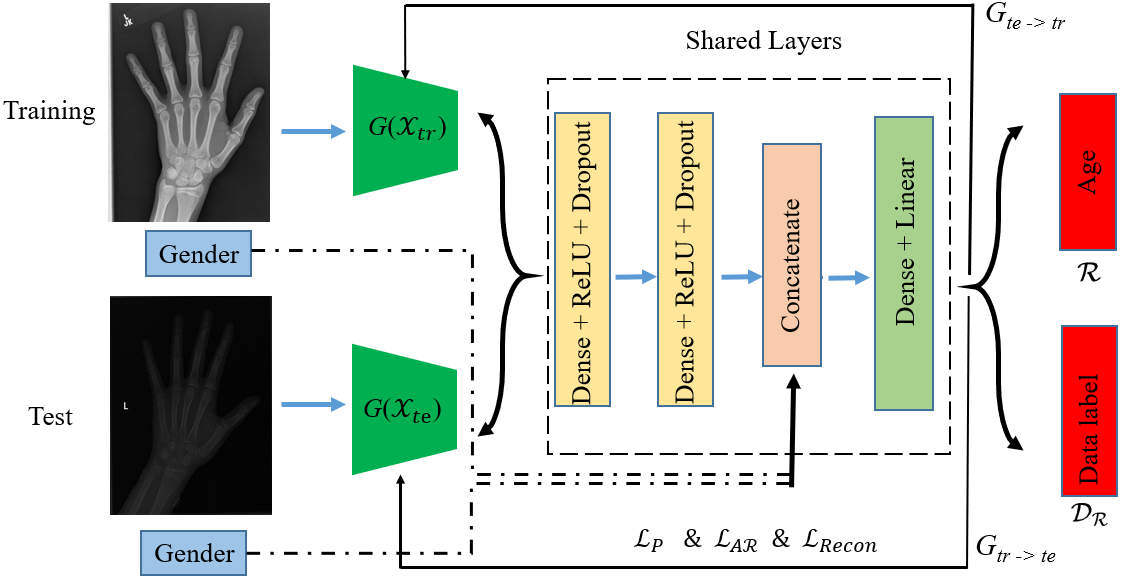

However, adversarial learning is typically applied in classification problems. The binary cross-entropy in Eq. 3 is also frequently used in improving the accuracy of classification problems. The cross-entropy loss is not proper to indicate the data difference in a regression problem. Therefore, we need a regression loss function to distinguish the training and test datasets, and we adopt the adversarial learning for the regression problem as follows.

where is adversarial regression loss, is the mapping from training to test data; is the adapted data regressor, and contains all training and test samples; is the data label in Fig. 2, specifically, is the label for the training data and is the label for the test data; is the prediction of data label; and denote the mean actual and predicted values of training or test dataset and is a small number (1e-9) to prevent division by 0. can measure how well-matched the training and test data are from both individual and overall differences. A perfect regression model would have an adversarial regression loss of 0.

To this end, the data regressor learns the data discrepancy by maximizing adversarial regression loss with the fixed , and the feature extractor aims to learn domain-invariant representations via minimizing with the optimal regressor . Eq. LABEL:eq:regre guarantees that , that is, given training samples, it will learn a map from training to test samples, while minimizing the in Eq. 2. However, Eq. LABEL:eq:regre only guarantees training data close to test data, and it does not ensure that maintains the features of the training samples. We hence introduce another mapping from test data to training data and train it with the same adversarial regression loss as in as shown in Eq. 5. The only difference is that the is the new data label for training data, and is the new data label for test data.

To encourage the training and test information to be preserved during the adversarial regression learning, we propose a feature reconstruction loss in our model. Details of the feature reconstruction layers are shown in Fig. 3; the reconstruction layers are right behind the shared layers, and it aims to reconstruct extracted features and maintain feature consistency during the conversion process without losing features. The feature reconstruction loss is defined as: